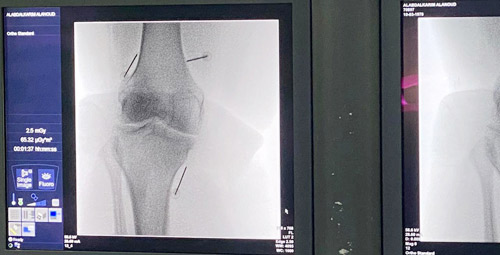

أعلنت مستشفى دلّه النخيل عن إجراء عملية غير جراحية بتقنية الكي بالتردد الحراري المبرد لامرأة ستينية عانت من آلام حادة في الركبة ناتجة عن حدوث خشونة في المفصل من الدرجة الثالثة. وتعد خشونة المفاصل من الأمراض الشائعة والمنتشرة انتشاراً واسعاً خاصة عند كبار السن، وهي عبارة عن حدوث تآكل في الغضروف الخارجي للمفصل وتلفه.

وبعد معاناة طويلة مع الألم وأشهر عديدة من العلاج الطبيعي وتناول أدوية لاستيرويدية مضادة للالتهاب دون جدوى، ونظراً لعدم رغبة المريضة في إجراء عملية جراحية لاستبدال الركبة بمفصل صناعي، عُرض على المريضة إجراء هذه العملية الجديدة نسبياً، بقيادة البروفيسور نزار عبدالعزيز النقشبندي، تم إجراء عملية الكي بالتردد الحراري المبرد تحت التخدير الموضعي، إذ لا تتطلب هذه العملية تخديراً كاملاً أو تدخلاً جراحياً. وتنطوي العملية على إدخال ثلاث أبر رفيعة يُدخل من خلالها مسبار كي التردد الحراري، ليتم ربط هذا المسبار مع جهاز يقوم بدوره بكَي العصب المغذي للركبة. وتسهم هذه العملية في تسكين الألم بنسبة لا تقل عن 70 في المائة لفتره قد تصل إلى سنتين.